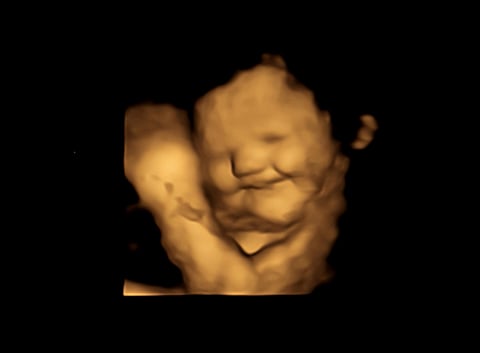

Scan from researchers of baby reacting with 'laughter' face after Mom ate carrot Photo: Fetal and Neonatal Research Lab, Durham University

Babies whose moms had consumed carrot showed more “laughter face” responses, while those who had tasted kale through their moms showed more “cry face” responses, the study authors said in a university news release.